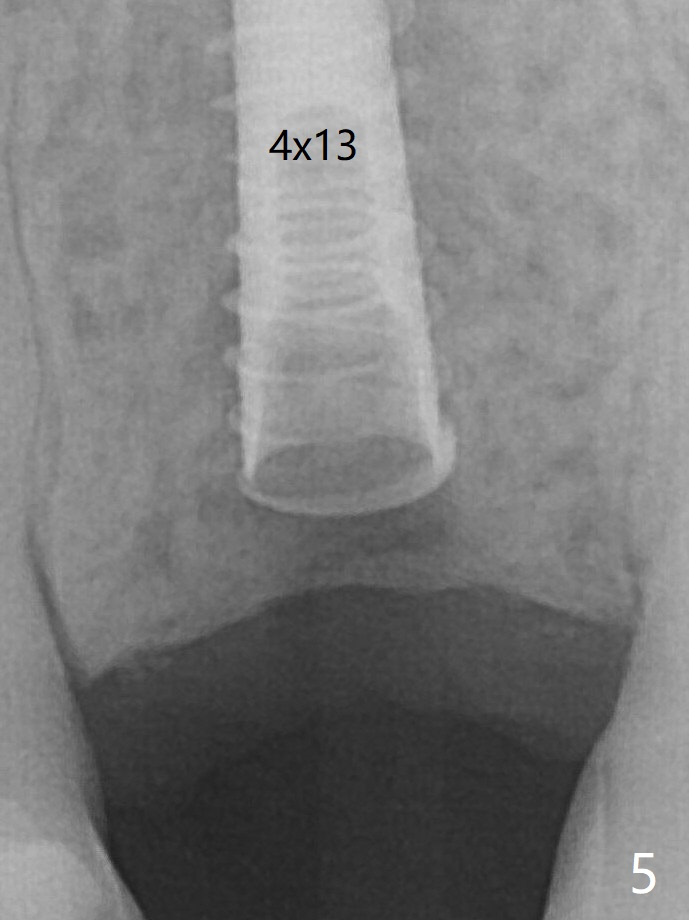

A 4x13 mm IBS implant is seated incompletely. The osteotomy is further enlarged by 3.8 mm Magic Drill for 11 mm and deepened with 3 mm drill until 18 mm. Finally the implant is placed at a satisfactory level with insertion torque > 50 Ncm (Fig.5). The patient chooses to return for impression 6 months postop (Fig.6). The abutment changes to a 4x4(4) mm one. The crown is recemented nearly 2 years post cementation, which is related to distal and deep placement of the implant and bruxism (Fig.7).